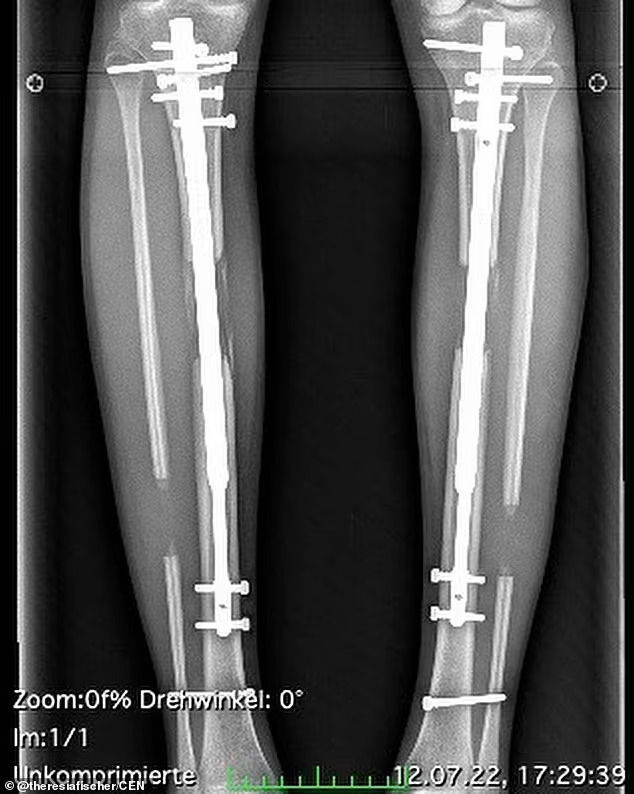

Người mẫu Đức chi gần 4 tỉ đồng để kéo dài chân. Theresia Fischer đã bỏ ra 128.000 bảng Anh (gần 4 tỉ đồng) để kéo dài chân thêm gần 14 cm. Cô nâng chiều cao của mình từ hơn 1,6 m lên gần 1,8 m

Cô khẳng định không biết gì về dịch vụ này cho đến khi nghe chồng cũ nói. Cô bắt đầu phẫu thuật đầu tiên khi 24 tuổi và kéo dài chân hơn 8cm mỗi bên.

Cô thực hiện hai cuộc phẫu thuật kéo dài xương chân

Sau đó, cô trải qua một cuộc phẫu thuật tiếp theo vào tháng 3-2022 để kéo chân dài thêm hơn 5cm. Chi phí cả hai lần phẫu thuật hơn 128.000 bảng Anh.